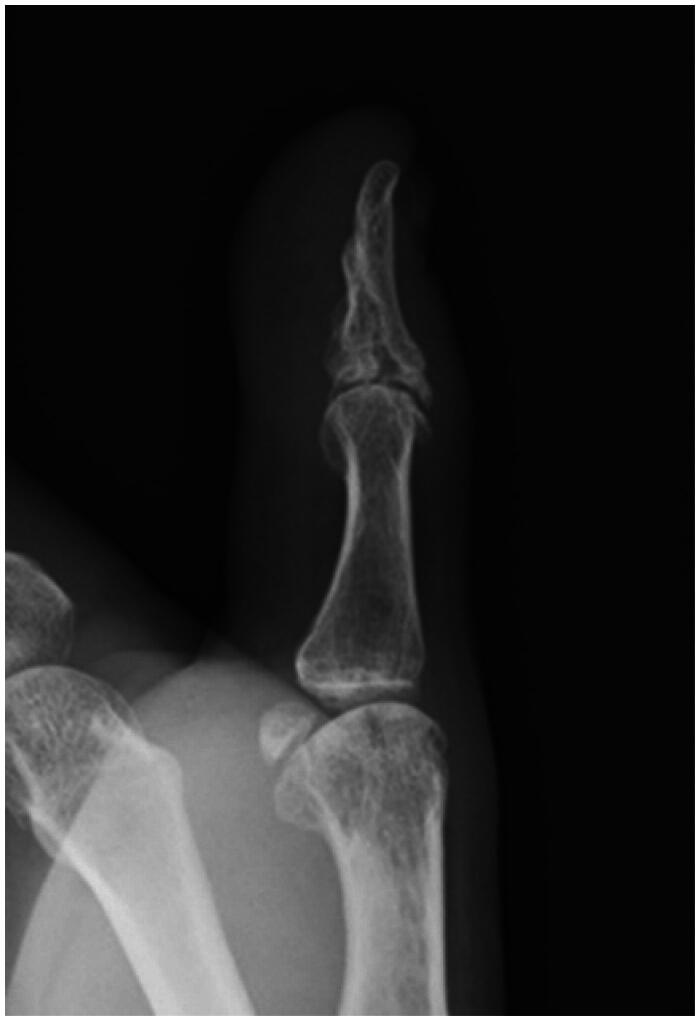

A distal phalanx may fracture in an atypical shape after high-energy trauma. A 61-year-old man sustained an open fracture of the distal phalanx of his left thumb while using a power saw. The fracture occurred in the coronal plane and the volar bone fragment was dislocated under traction by the flexor pollicis longus tendon. The patient underwent surgery the day after the injury. A flexion block pin was inserted to reduce the volar bone fragment, and an external flexion force was applied using a dorsal splint to compress the dorsal bone fragment into the volar bone fragment. The pin was removed 6 weeks postoperatively, and active range of motion exercises were started 8 weeks postoperatively. Bone union was achieved with good alignment, and although the interphalangeal joint remained slightly restricted in range of motion, the patient returned to his previous job and was satisfied with the function of the left thumb.

高能创伤后远端指骨可能以非典型形状骨折。一名61岁男子在使用电锯时左手拇指远端指骨开放性骨折。骨折发生在冠状面,掌侧骨碎片在拇长屈肌腱牵引下脱位。病人在受伤后的第二天接受了手术。插入屈曲块销以复位掌侧骨碎片,并使用背侧夹板施加外部屈曲力将背侧骨碎片压缩到掌侧骨碎片中。术后6周取下固定针,术后8周开始活动范围训练。骨愈合,对准良好,虽然指间关节的活动范围仍有轻微限制,但患者恢复了原来的工作,并对左手拇指的功能感到满意。